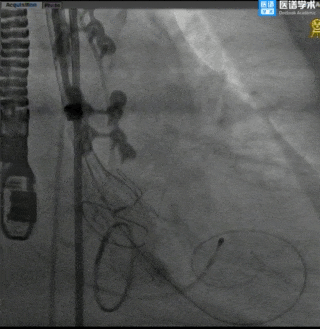

TaurusElite®最终释放形态

术后评估

主动脉瓣术后平均压差7mmHg,无瓣周漏。

对本例手术,修建成教授团队通过术前详尽的检查分析评估,对可能发生的各种突发情况进行充分预估,并准备了相应的应对预案,手术中采用左前斜头位体位,较高位释放(0-2mm),术后跨瓣压差降至7mmHg,血流动力学得到有效改善,为患者带来更长久的生存预期和更高的生活质量。本例手术的成功开展再次展现了修建成教授团队在诊治高难度复杂主动脉瓣膜疾病的雄厚实力和丰富经验,为临床上解剖异常、情况复杂的患者行TAVR治疗提供了更多的参考,也为外科生物瓣膜毁损后的老年高危心脏瓣膜病患者的治疗提供更多的信心!